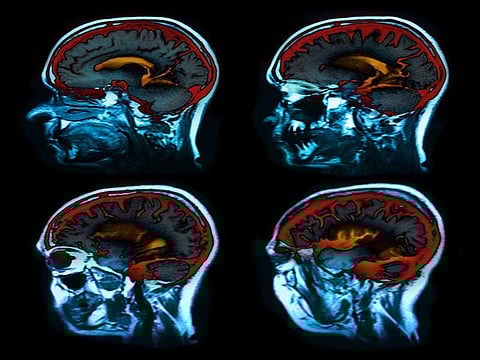

Deep brain stimulation uses electrodes placed in areas of the brain to control Parkinson's symptoms. The electrodes connect to a pacemaker-like device placed under the skin in the upper chest that transmits an electrical pulse that helps to control symptoms. Many patients use a handheld controller to adjust stimulation levels as needed.